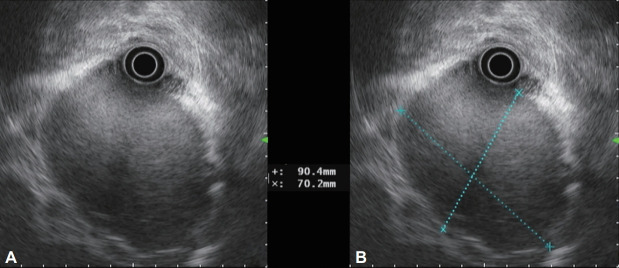

一名48岁男性来我院评估黑黑症。腹部计算机断层扫描(CT)显示胃底和上半身有一个内生增强肿块(约9厘米)。CT未见其他器官转移。内窥镜检查发现一个大肿块,伴有渗出物和表面出血的迹象。肿块的形状类似于上皮下肿瘤,约50%的粘膜脱落。内窥镜超声检查显示高回声扩散和大夫棒状无回声病变排列在整体低回声肿块内。患者行全胃切除术并淋巴结清扫,诊断为未分化多形性肉瘤,无淋巴结转移。未分化多形性肉瘤是一种高度侵袭性软组织肉瘤,主要累及四肢,很少发生胃。它通常是无症状的,但往往迅速增长。表现前一年的内窥镜成像无显著性。我们报告一例胃未分化多形性肉瘤,表现为快速生长的上皮下肿瘤。快速生长的胃上皮下肿瘤患者在鉴别诊断时应考虑胃肠道间质肿瘤以外的恶性肿瘤。

A 48-year-old man presented to our hospital for evaluation of melena. Abdominal computed tomography (CT) revealed an endophytic contrast-enhanced mass (approximately 9 cm) in the gastric fundus and upper body. CT showed no evidence of metastasis to other organs. Endoscopic examination revealed a large mass accompanied by an exudate and signs of surface hemorrhage. The shape of the mass resembled that of a subepithelial tumor, and >50% of the mucosa was peeled off. Endoscopic ultrasonography revealed hyperechoic spreading and dotor rod-shaped anechoic lesions arranged within an overall hypoechoic mass. The patient underwent total gastrectomy with lymph node dissection and was diagnosed with undifferentiated pleomorphic sarcoma without lymph node metastasis. Undifferentiated pleomorphic sarcoma, a high-grade aggressive soft tissue sarcoma, predominantly involves the extremities and rarely the stomach. It is usually asymptomatic but tends to grow rapidly. Endoscopic imaging performed a year prior to presentation was unremarkable. We report a case of a gastric undifferentiated pleomorphic sarcoma that presented as a rapidly growing subepithelial tumor. Malignancies other than a gastrointestinal stromal tumor should be considered in the differential diagnosis in patients presenting with a rapidly growing gastric subepithelial tumor.